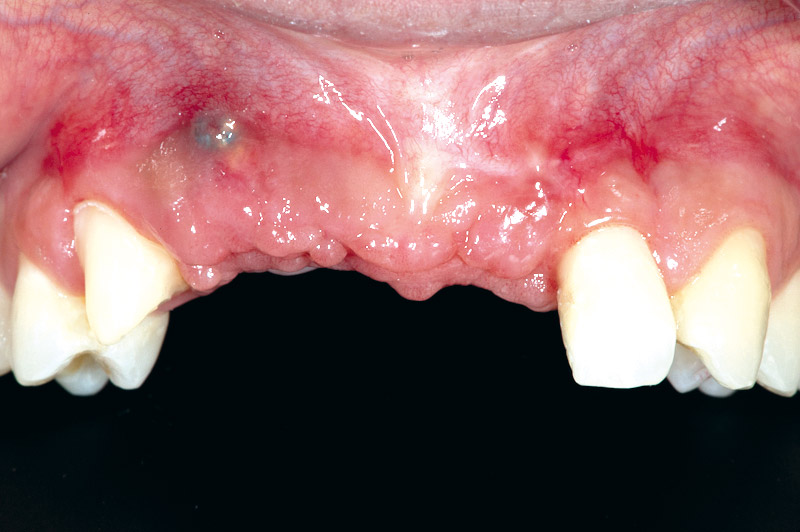

01/17 - Initial situation before surgery. Patient lost central incisors 1 month ago due to endodontic failures

Block augmentation with maxgraft® block & mucoderm® - Dr. K. Chmielewski